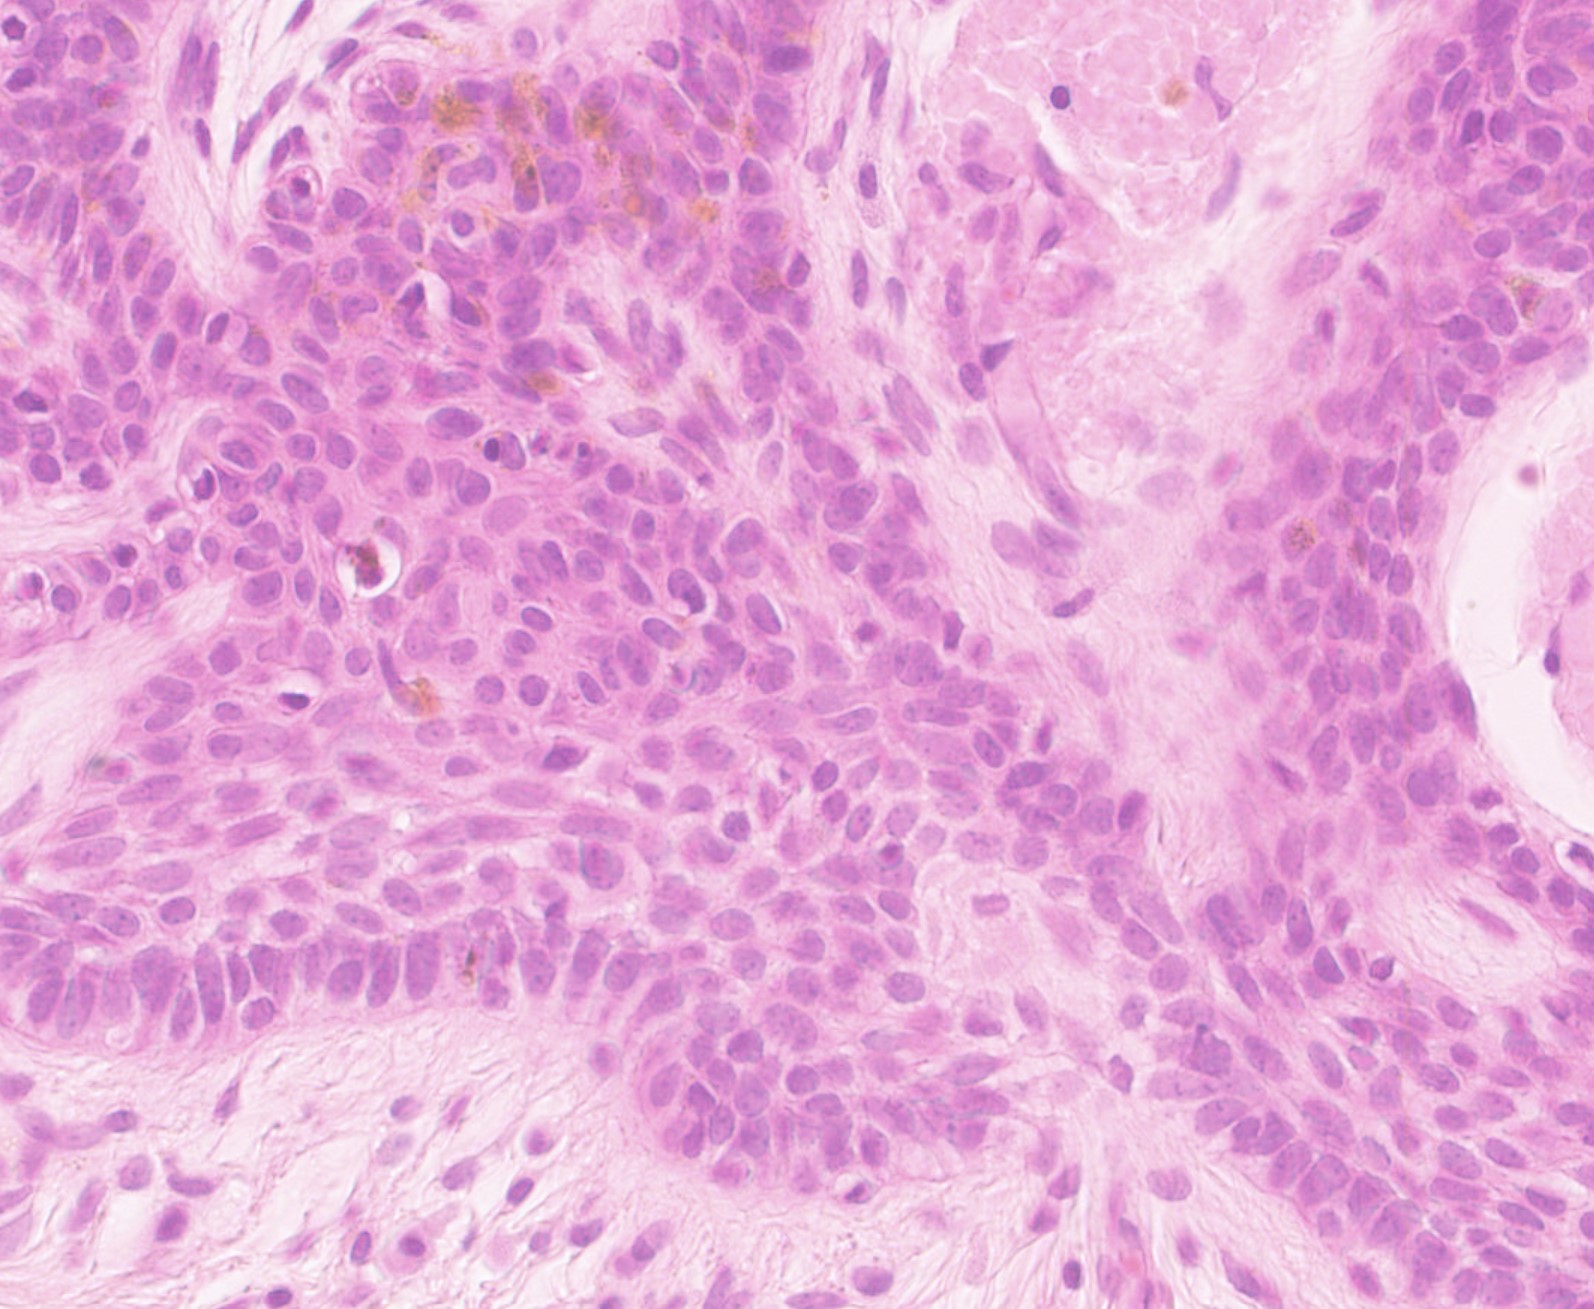

Male 70